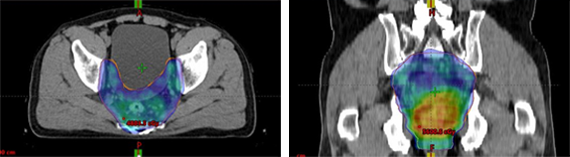

并且,Halcyon 的机架转速提高到过去的4倍,MLC 运行速度提高到过去的2倍,能够在更短时间内实现多野 IMRT 或多弧 VMAT 治疗,更好保护临近危及器官,特别是复杂的鼻咽癌、盆腔肿瘤等放疗,例如山东肿瘤医院4弧 VMAT 治疗宫颈癌,更好保护膀胱和直肠等正常组织,放疗出束时间只有2分钟。

Halcyon 系统实现临床放疗价值突破性进展

图片来自山东省肿瘤医院